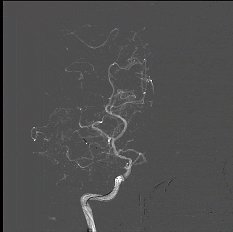

CTA

image.png  image.png

DSA

8月25日.gif